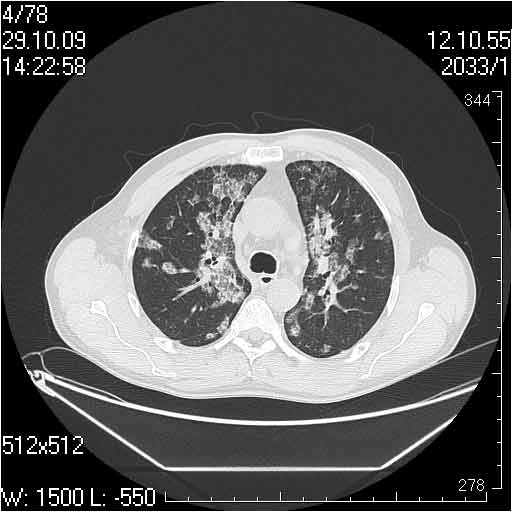

Случай №1

Женщина 50 лет.

Случай 1: изменения характерны для интерстициальной пневмонии (IIP/UIP idiopathic interstitial pneumonia/usual interstitial pneumonia); говорить о конкретной форме без открытой биопсии затруднительно.